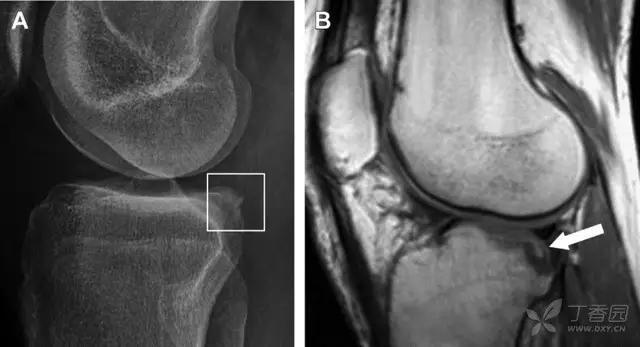

12 反向 Segond 骨折

胫骨平台内侧皮质骨撕脱性骨折,被称为内侧 Segond 骨折或反向 Segond 骨折(图 5)。这种骨折的旋转机制与 Segond 骨折相反,该骨折与后交叉韧带断裂及内侧半月板损伤相关。

图 5 一位足球运动员的反向 Segond 骨折

A 正位片示关节线处的胫骨内侧见一细小骨折片(箭头)。B MRI 冠状位 T1 加权像示骨折片出现在内侧副韧带关节囊附着处(方框)。